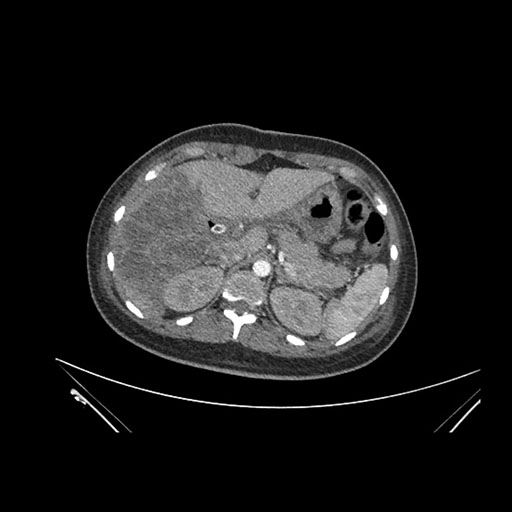

Axial Venous

Imaging analysis

Based on initial findings, which issue(s) would you be most concerned about?